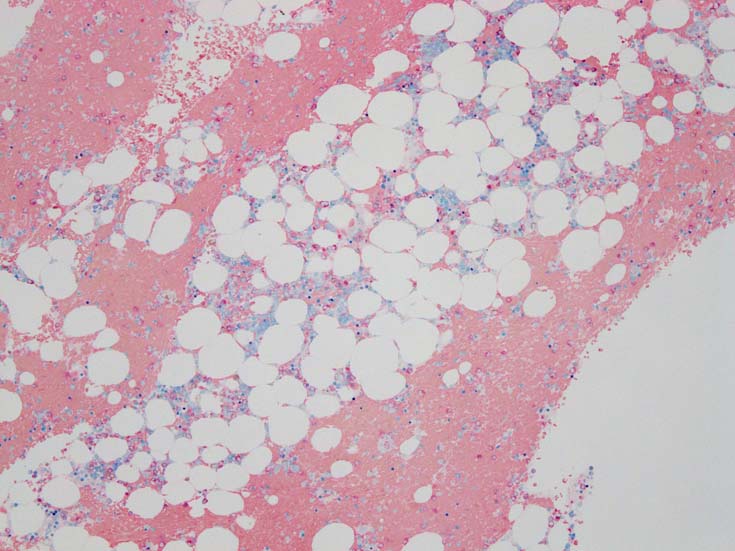

MDS症例のHbF発現.

サムネイル画像をクリックすると大きな画像が見られます.

MDSでの赤芽球HbF発現は, 陽性細胞はそれほど多くない印象ですが, この低形成性MDS症例では, 多くの陽性細胞がaggregatesを形成していました.